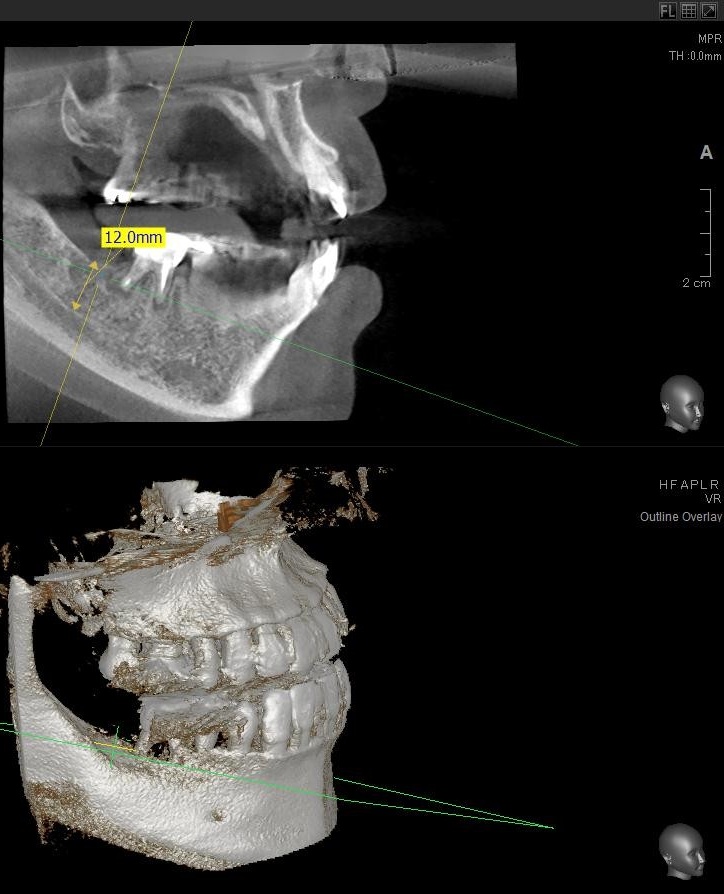

今回の患者様はインプラント植立を希望され、右下7番目の植立が決まりました。

開けた穴に、専用道具を使ってネジを締めるように長さ2センチ程のインプラントを骨に埋め込んでいきます。

しっかりとインプラント埋め込まれた後は、動揺がないか、噛んだ時に当たらないかなどを確認して、最後にパノラマ写真を撮影して今回のオペは終了となりました。